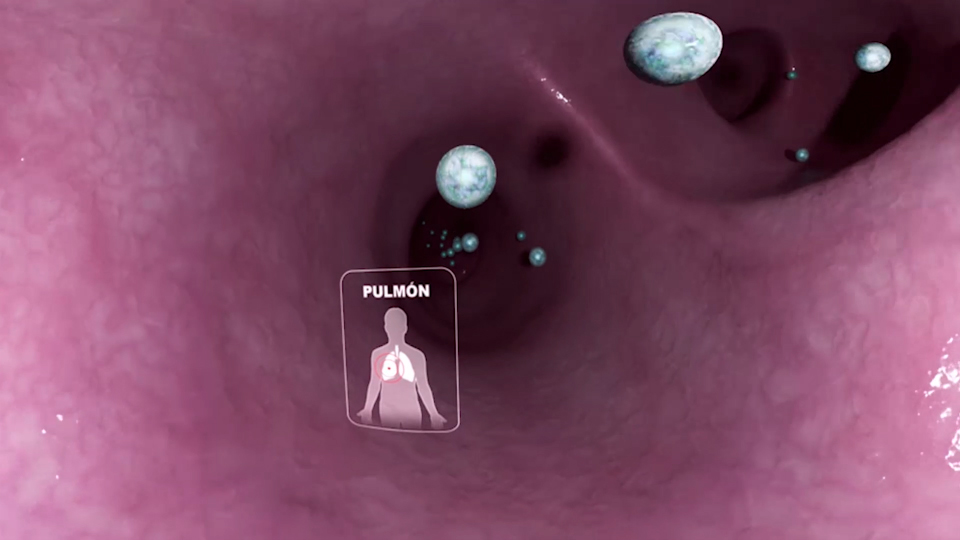

MECANISMO DE ACCIÓN

Render 3D estereoscópico 360

Mecanismo de acción de diferentes fármacos de varias áreas médicas. Viaje dentro del cuerpo humano viendo cómo funcionan los diferentes fármacos dentro del cuerpo desde un nivel celular hasta nivel molecular. Se visionó en diferentes congresos y reuniones internas para médicos en Samsung Gear VR y Oculus Rift.